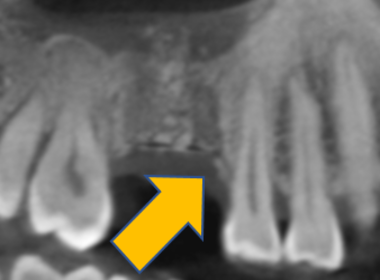

| 0220 #46#47 右下第一第二大臼齒 |

![]() |